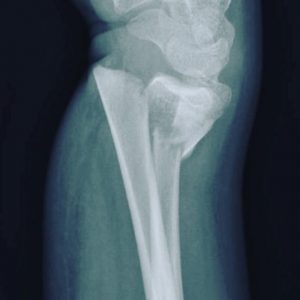

- Fracturas de codo

- Fractura supracondílea

- Fractura de cóndilo humeral

Fractura distal de radio

fractura de condilo humeral

Fractura supracondílea de humero

Fractura radiocubital

Fractura de radio distal